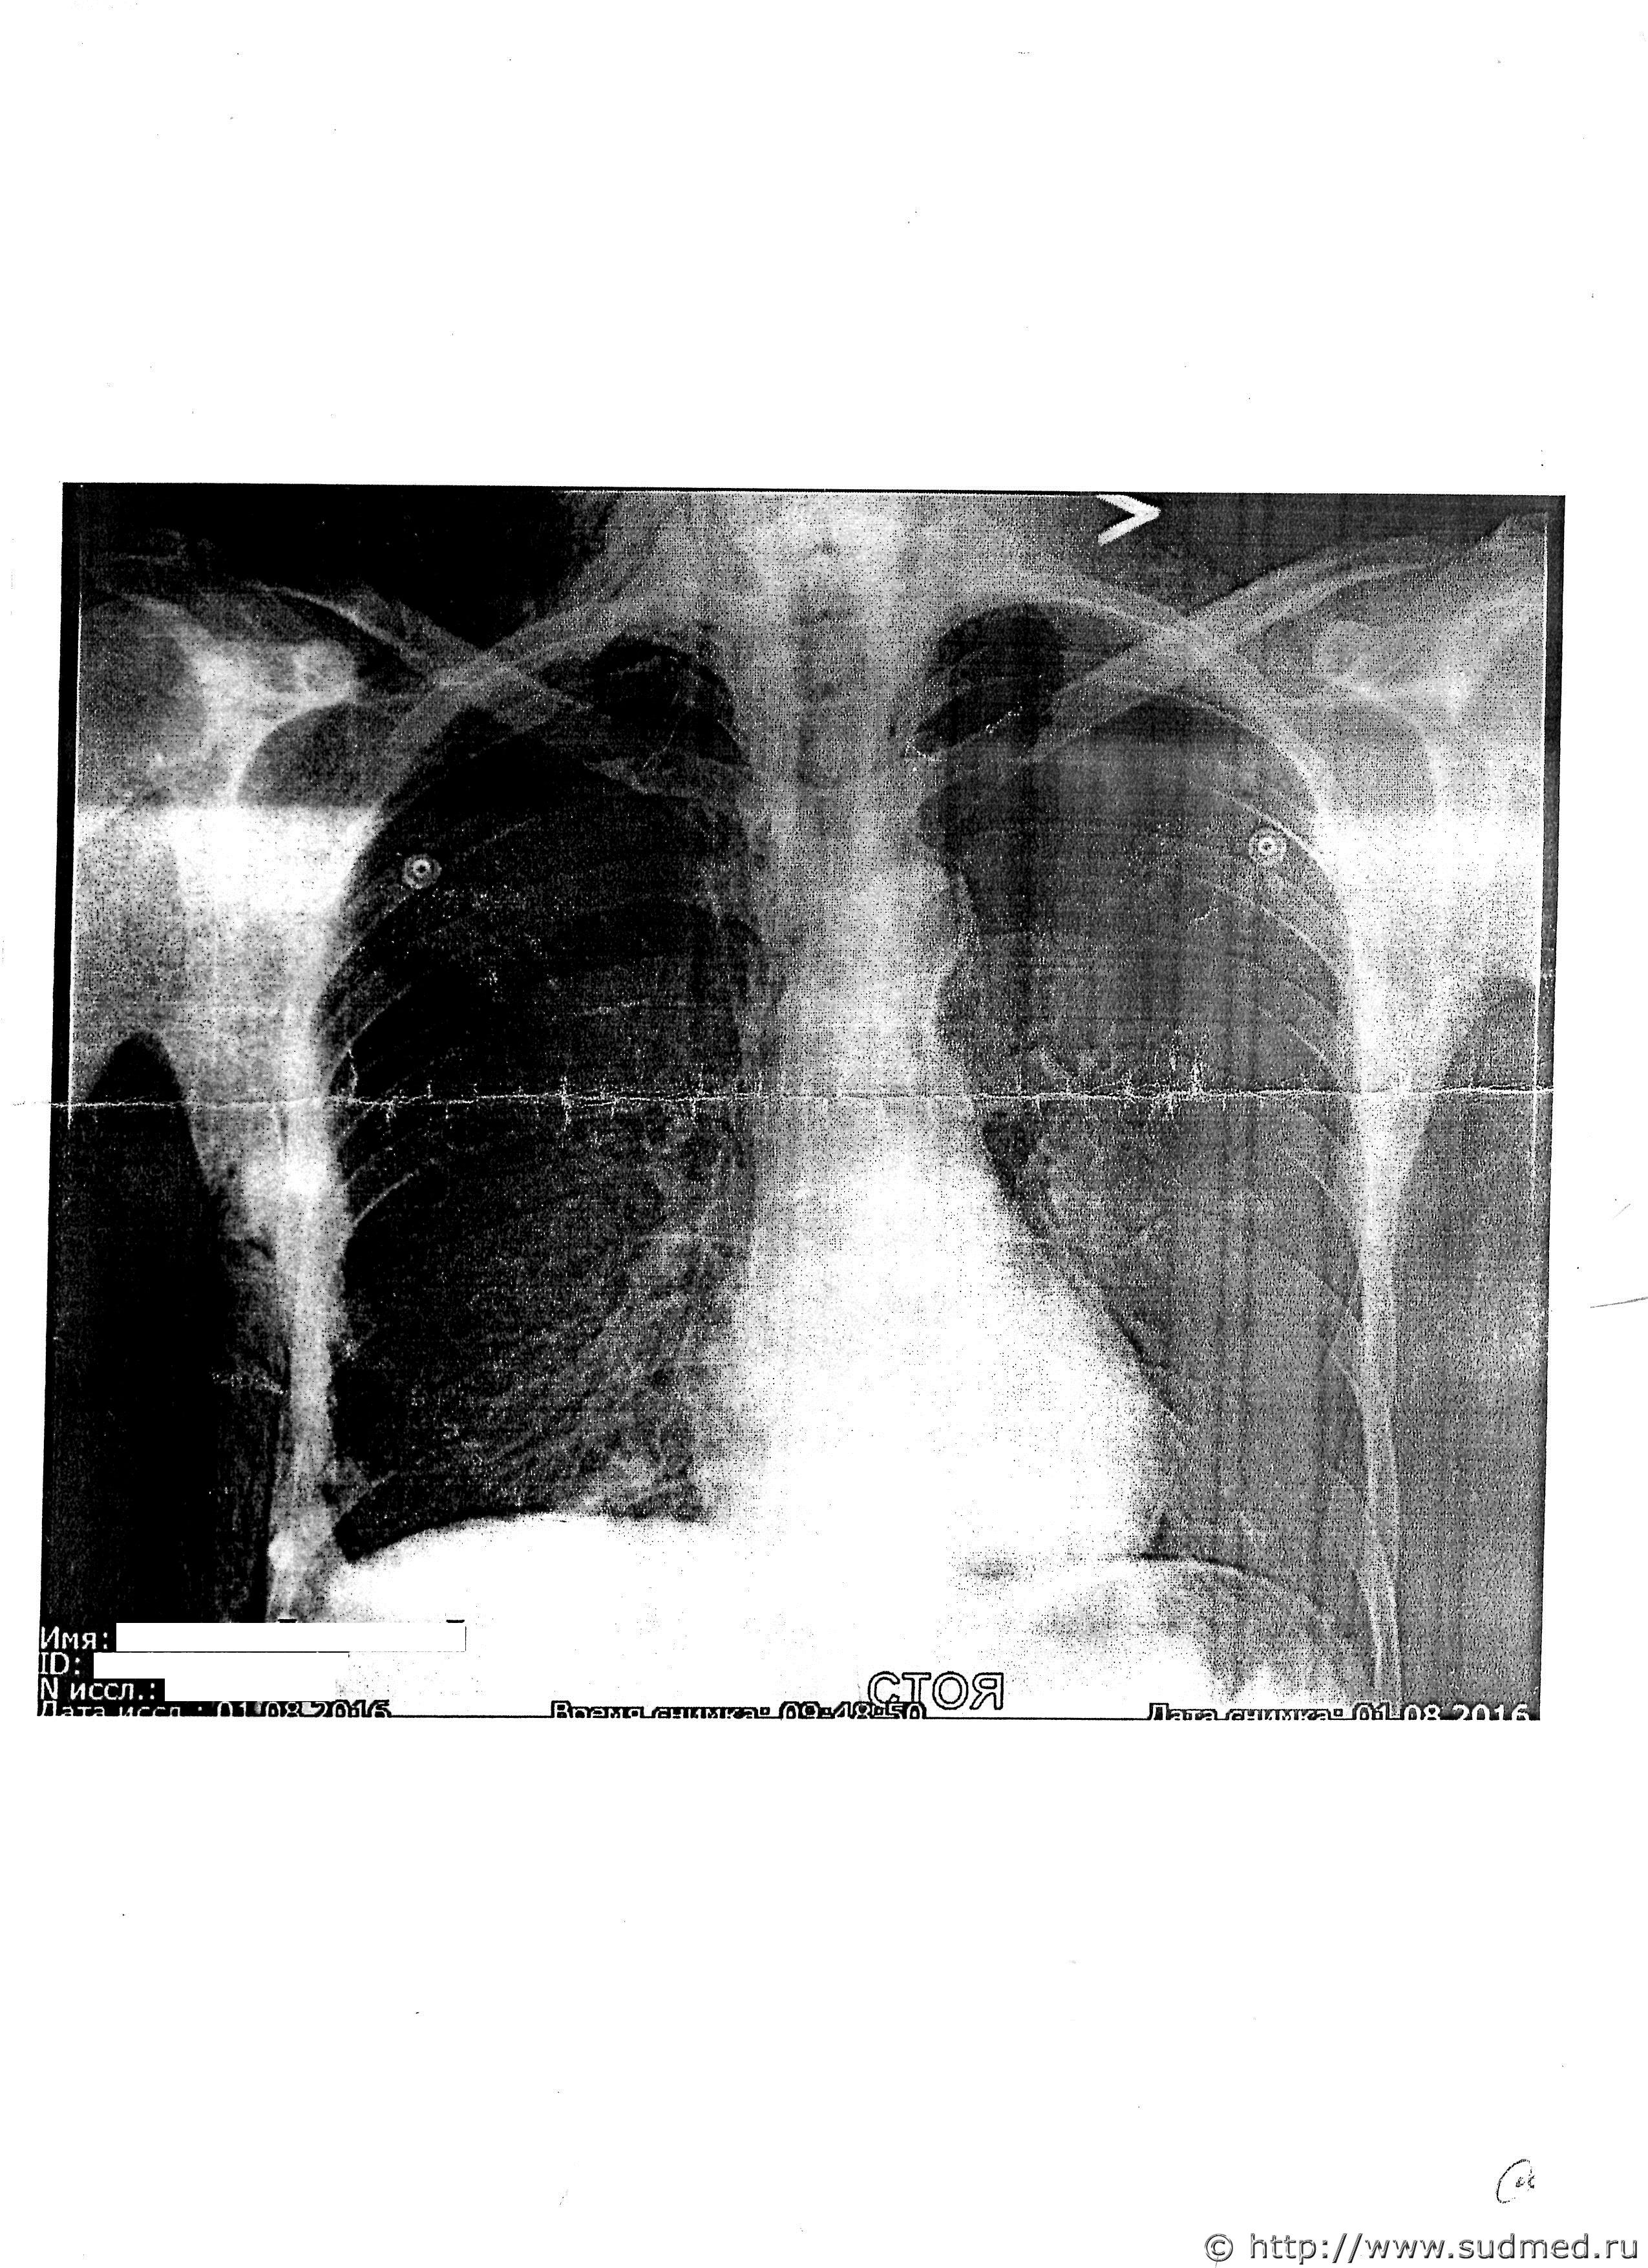

Доброго времени суток. Очень буду признателен мнению экспертов. Вот появились снимки и возникли вопросы по ним.

1. Подскажите, пожалуйста, можно определить повреждение и имеется ли разрыв лёгкого?

2. Может ли такое повреждение быть связано с повреждением париетальной плевры без повреждения самого лёгкого?

4.Можно ли по снимку определить - это пневмоторакс либо иное травматическое или посттравматическое явление?

5. Могло ли такое повреждение образоваться при падении с высоты собственного роста с приданием телу дополнительного ускорения (от удара)?

6. Могли ли переломы 5-8 ребер по средней подмышечной линии возникнуть от ударов кулаками лежащему на земле на левом боку человеку?

7. От чего могли образоваться такие переломы?

Судебная медицина - Прикрепленное изображение Судебная медицина - Прикрепленное изображение Судебная медицина - Прикрепленное изображение

3. Переломы с пятого по восьмое ребро по средней подмышечной линии справа не могли образоваться при падении с высоты собственного роста на плоскость.

4. Фактически здесь есть: достоверные рентгенологические признаки пневмоторакса (воздух в плевральной полости из-за разрыва легкого), клинические признаки дыхательной недостаточности (одышка), обширная эмфизема мягких тканей груди, видимая на рентгенограммах и наблюдавшаяся клинически. Вполне достаточный комплекс клинико-рентгенологических признаков.

7. Считаю, что нарастающий пневмоторакс (являющийся признаком разрыва легкого) с признаками дыхательной недостаточности (одышка до 24, бледен - на фоне алкогольного опьянения!) - достаточное основание считать травму опасной для жизни. То, что травма не закончилась смертью - случай, а закономерный исход - с высокой вероятностью печальный (про это есть много в клинической и судебно-медицинской литературе). На самом деле, тут есть о чем подискутировать в процессе, показывая перед клиентом работу защитника, но поменять вред не получится.